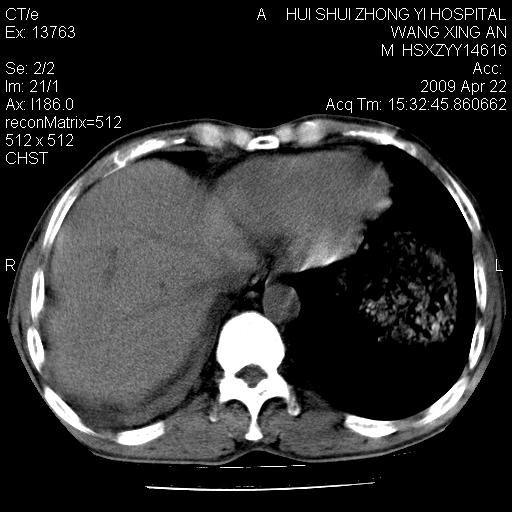

标题: CT19534:患者男、46岁咳嗽、胸痛半月。 [打印本页]

标题: CT19534:患者男、46岁咳嗽、胸痛半月。

1、右下肺中央型肺癌并右肺转移,右肺中下叶不张。(右肺有结节影)。胸骨转移

1。右下肺中央型肺癌并肺转移,右肺下叶不张。(两肺都有结节影)。

1)右肺中间段支气管癌并右肺下叶肺不张。2)右肺上叶、两肺下叶背段感染性病变。3)右侧少量胸腔积液。